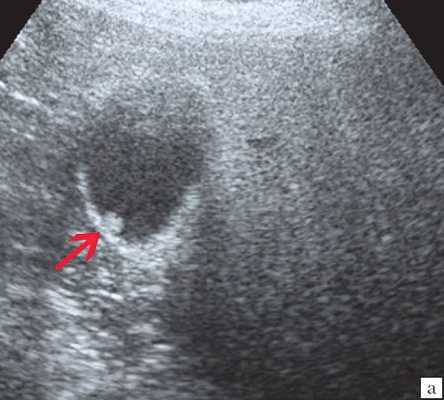

Ультрасонография является эффективным средством выявления полиповидной формы холестероза 9. Традиционной считается следующая сонографическая характеристика холестериновых полипов: неподвижные гиперэхогенные структуры, которые не дают акустической тени и прикрепляются к стенке желчного пузыря. Контуры таких образований, как правило, ровные, а размеры таких образований различны, чаще не превышают 10 мм (рис. 2).

![Эхограмма - одиночный полип в желчном пузыре (2а)]()

a) Одиночный полип в желчном пузыре (гиперэхогенное пристеночное неподвижное образование, с ровными контурами, без акустической тени).

![Эхограмма - одиночный полип в желчном пузыре (2б)]()

б) Одиночный полип в желчном пузыре.